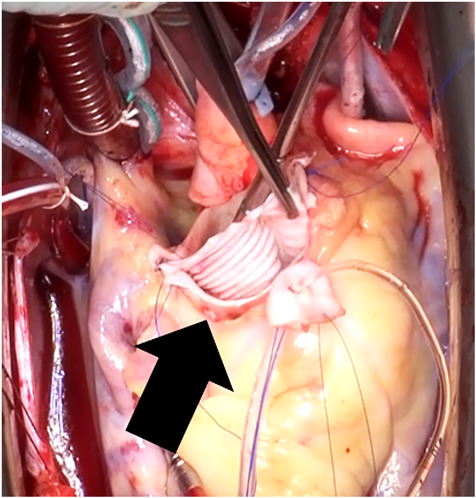

Fig. 2 手術所見

温存した右バルサルバ洞瘤壁(矢印)の内側の大動脈弁輪にトリミングした人工血管パッチを縫着し,右バルサルバ洞を形成した.